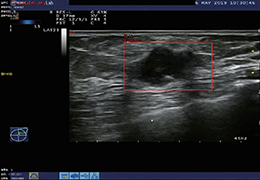

成像智能。

Eclipse 成像智能功能提供强大的处理能力和最佳质量的影像,同时减少质量错误并提高剂量效率。

凭借 AI、专有算法和先进的影像处理能力,提供出色的影像质量和无与伦比的诊断信心。

与标准影像处理相比,智能降噪功能可使客户降低辐射剂量,而不会损失影像质量。这在新生儿和儿科成像中尤其重要,在这种情况下以尽可能低的剂量成像至关重要。